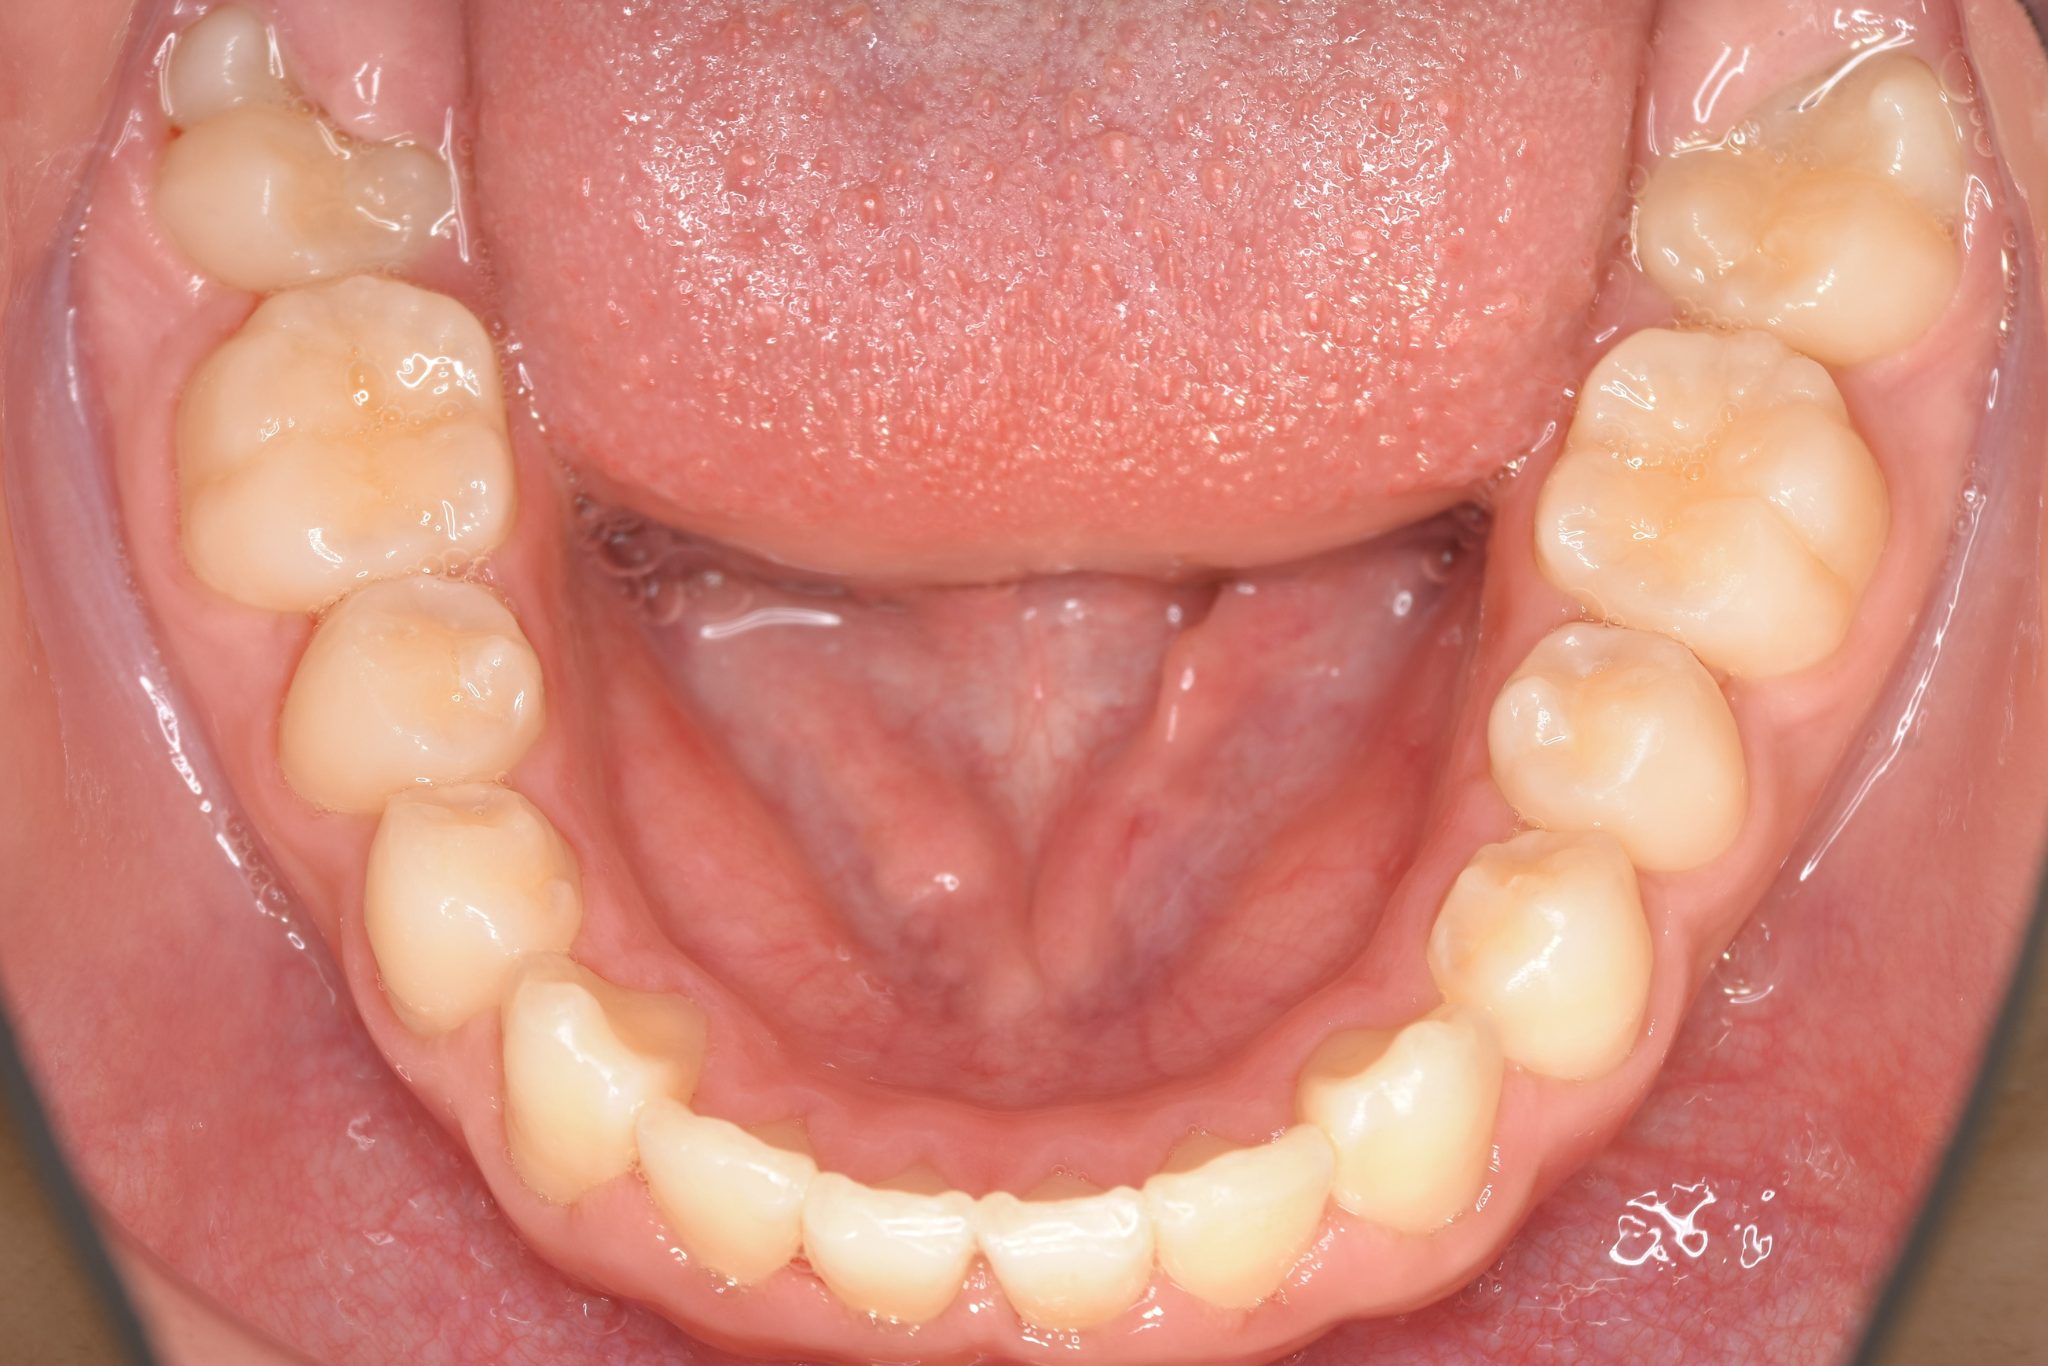

ビフォー

全顎ワイヤー矯正 症例_218